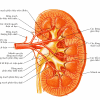

– Thận hình hạt đậu nằm phía sau ổ phúc mạc, 2 bên cột sống.

– Kích thước: dày 3cm, rộng 6cm, cao 11cm. Trọng lượng: 150gram (nam) và 135 gram (nữ).

– Rốn thận chứa mạch máu ra-vào thận và niệu quản.

– Ngoài cùng là mạc thận, bản chất là mô liên kết, gồm 2 lá (trong và ngoài). Tiếp đến là lớp mỡ quanh thận, rồi đến bao thận và cuối cùng là nhu mô thận.

– Động mạch thận: thận được cấp máu bởi động mạch thận, tách ra từ động mạch chủ bụng. Động mạch thận phải đi phía sau tĩnh mạch chủ dưới. Động mạch thận vào thận qua rốn thận, sau đó chia làm nhiều nhánh – chia các động mạch liên thùy – chia thành nhiều động mạch cung.

– Cấu tạo thận: xoang thận ở giữa – xung quanh là nhu mô thận (vỏ thận + tủy thận)

+ Xoang thận: chứa mạch máu và thần kinh thận, hệ thống đài bể thận và mô liên kết mỡ. Đài thận nhỏ nhận nước tiểu từ nhú thận, đổ ra đài thận lớn, đài thận lớn hợp thành bể thận – nối với niệu quản.

+ Vỏ thận: nằm ngay dưới bao thận, gồm cột thận (giữa các tháp thận) và các tiểu thùy vỏ từ đáy tháp thận tới bao thận.

+ Tủy thận: do các tháp thận (tháp Malpighi) tạo nên. Đáy tháp thận hướng về phía vỏ thận, đỉnh hướng về phía xoang thận, lồi vào trong xoang thận tạo nên nhú thận – nối với đài thận nhỏ.